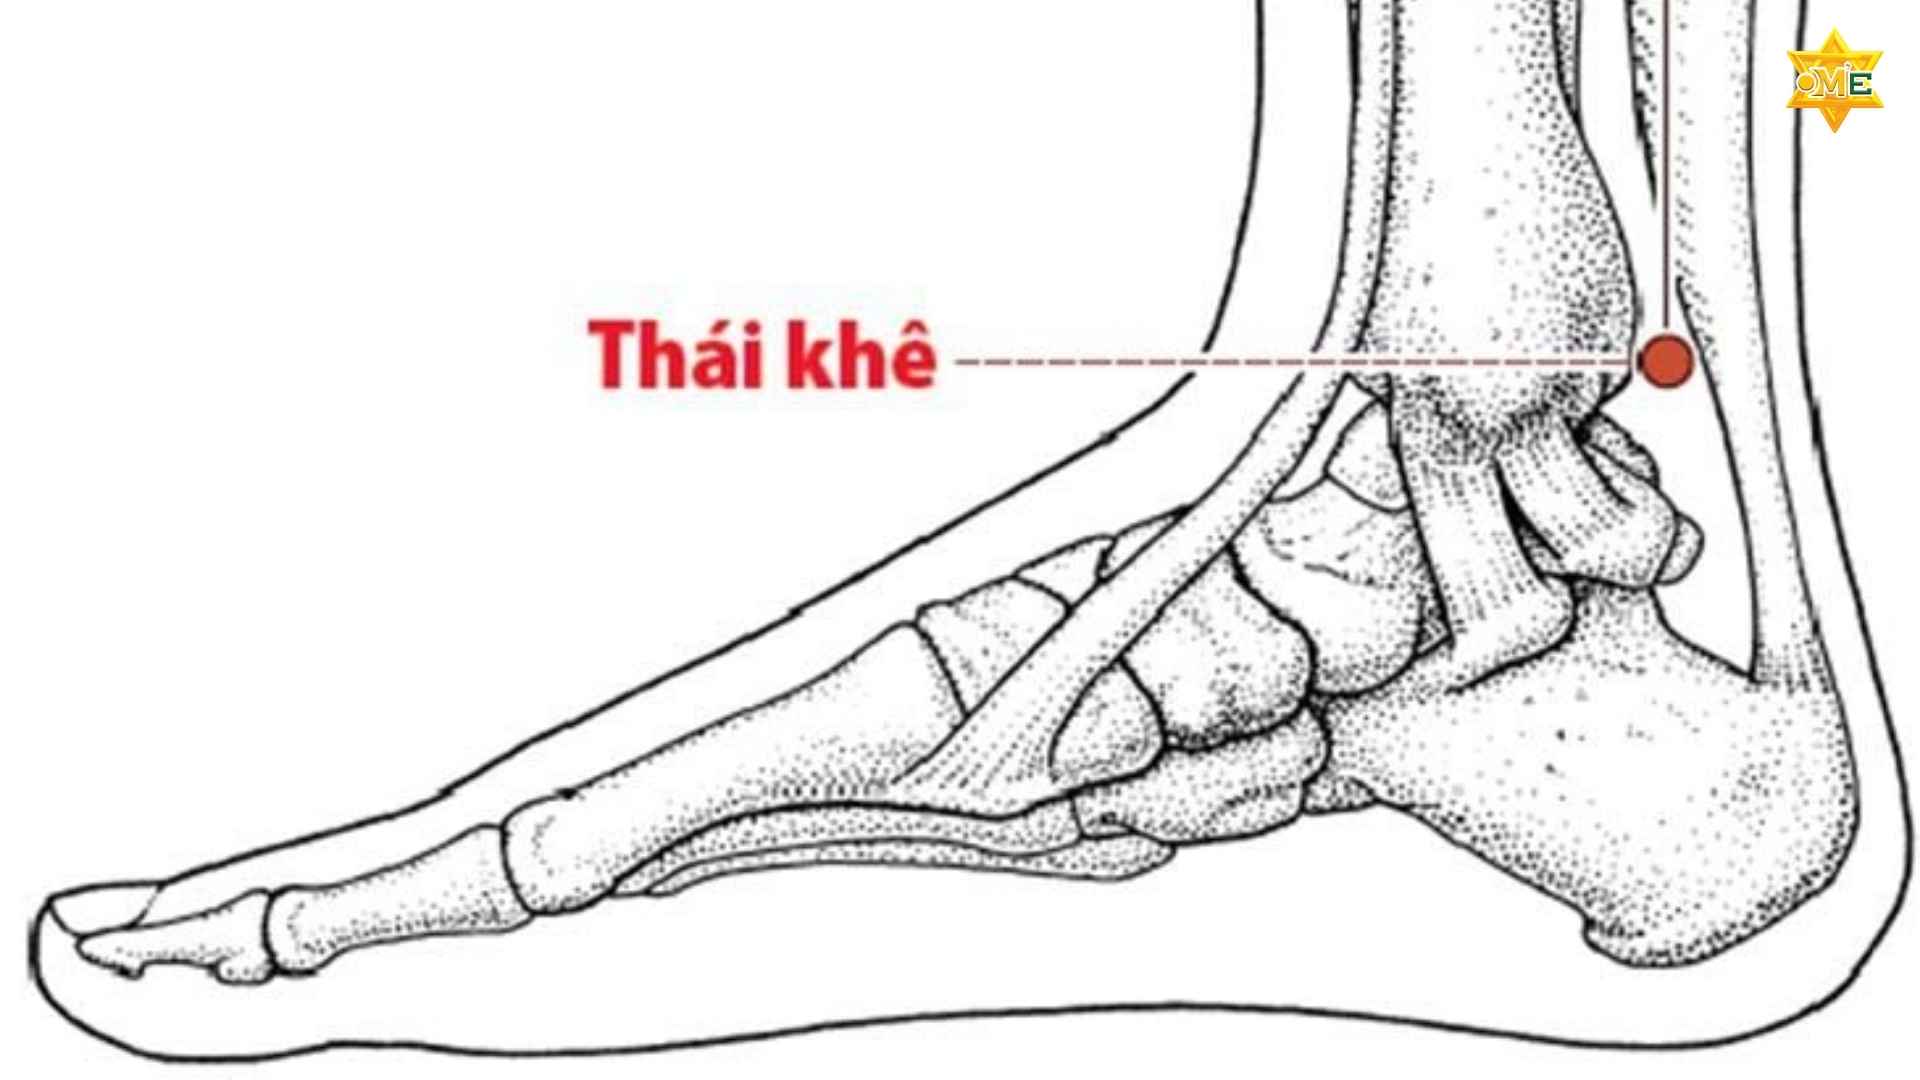

Về mặt giải phẫu y học, vị trí của huyệt Thái Khê nằm ở vùng cổ chân, cụ thể là ở phía mặt trong. Huyệt tọa lạc tại điểm trung điểm giữa đường nối bờ sau của mắt cá chân trong và mép trong của gân gót (gân Achilles). Đây là vùng có động mạch chày sau đi qua, do đó khi đặt tay vào đúng vị trí này, bạn thường sẽ cảm nhận được mạch đập nhẹ.

Việc nắm vững cấu trúc giải phẫu này là nội dung bắt buộc trong các khóa học xoa bóp bấm huyệt Tại OME Việt Nam, các chuyên gia luôn nhấn mạnh rằng Thái Khê nằm ở “vùng trũng” nhất, nơi hội tụ khí huyết của kinh Thận trước khi luân chuyển đi khắp cơ thể.

- Bước 2: Tìm điểm mốc: Đầu tiên, bạn dùng ngón tay trỏ tìm điểm cao nhất của mắt cá chân trong (phần xương lồi ra ở phía trong cổ chân). Tiếp theo, bạn xác định dải gân lớn ở phía sau gót chân (gân gót). Cách xác định huyệt Thái Khê chuẩn nhất là tìm điểm lõm nhất nằm chính giữa hai điểm mốc này.

3. Quan sát hình ảnh huyệt Thái Khê trong tâm trí

Mặc dù việc nhìn qua hình ảnh huyệt Thái Khê trên các sơ đồ huyệt vị là rất cần thiết, nhưng việc tự cảm nhận trên chính cơ thể mình mới mang lại sự chính xác tuyệt đối. Bạn hãy tưởng tượng huyệt Thái Khê như một cái hồ chứa nước nhỏ nằm nép mình sau chân núi (mắt cá chân) và trước một con đường lớn (gân gót).

Khi quan sát hình ảnh huyệt Thái Khê trên các sơ đồ giải phẫu, bạn sẽ thấy nó nằm ở vùng trũng nhất của cổ chân. Cách xác định vị trí huyệt Thái Khê chuẩn nhất là khi bạn dùng ngón tay ấn nhẹ vào vùng này và cảm nhận được mạch đập của động mạch chày sau. Sự chính xác trong việc tìm huyệt sẽ quyết định tới 80% hiệu quả của quá trình xoa bóp bấm huyệt.